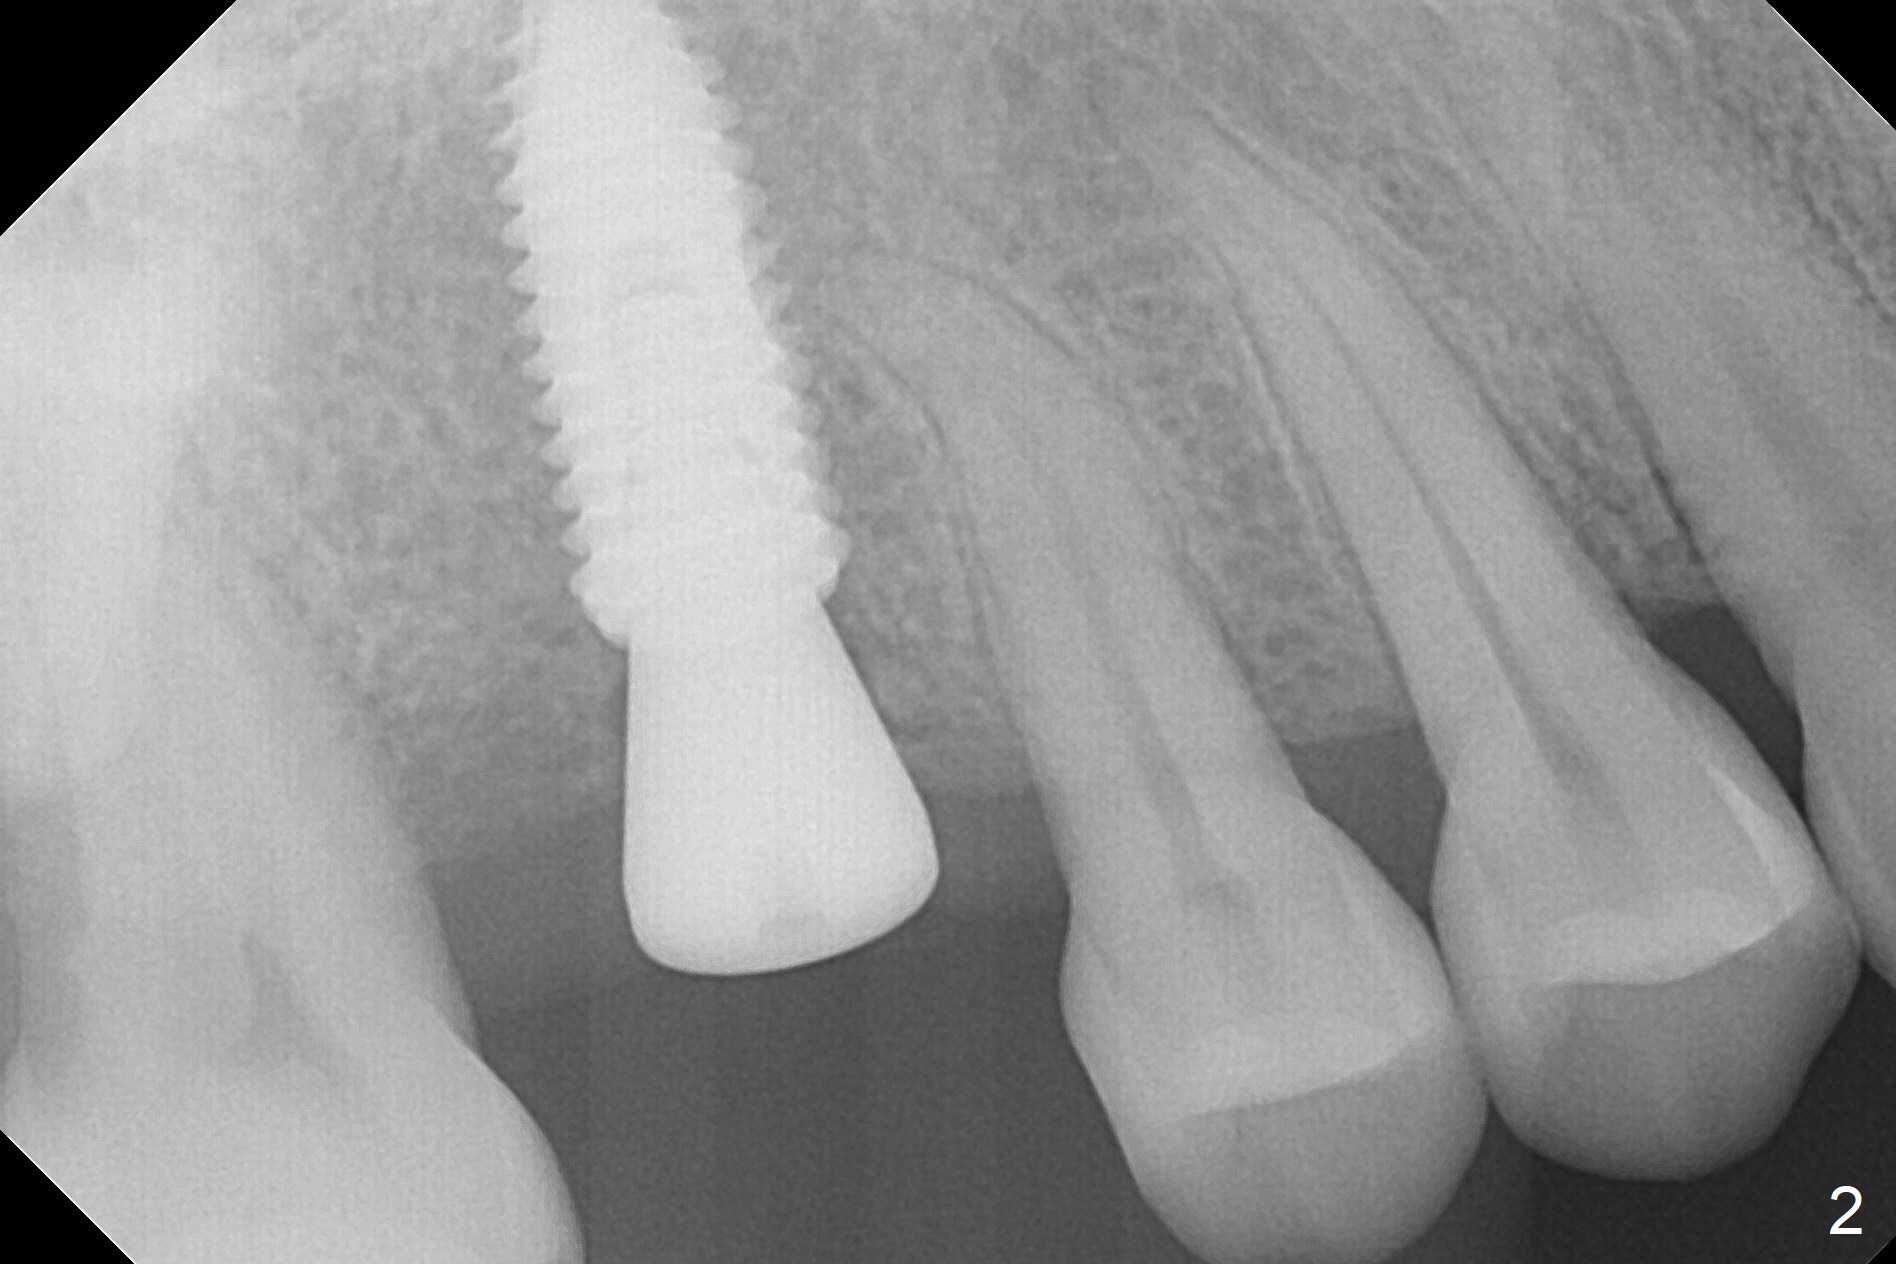

In order to place a 5x11.5 mm implant at #3 completely in depth, the preop CBCT coronal section is reanalyzed (Fig.1). It appears that extra 1 mm osteotomy does not perforate the sinus floor. After finishing osteotomy according to the guide plan, a 3.5x13 mm drill is used ~ .5 mm shy of the depth without sign of sinus membrane leakage. The implant is placed with apparently satisfactory depth, but it is quite close to the curved root tip of the neighboring tooth (Fig.2,3). In fact postop CBCT shows that there is a clearance (Fig.4). To prevent the similar event in the future, the implant should be designed slightly distal. The postop CBCT also shows that the extra depth is not necessary (Fig.4 *); it seems that the inherent 1.2 mm drill tip is sufficient for the depth overprep. The implant is stable for impression 6.5 months postop (Fig.5), whereas that placed immediately free hand is unstable 7.5 months postop. Two weeks later, the patient experiences severe pain when the abutment is being retightened. The crown at #3 is delivered 3 months later (9 months postop). It appears that the bone heals slow in this patient.